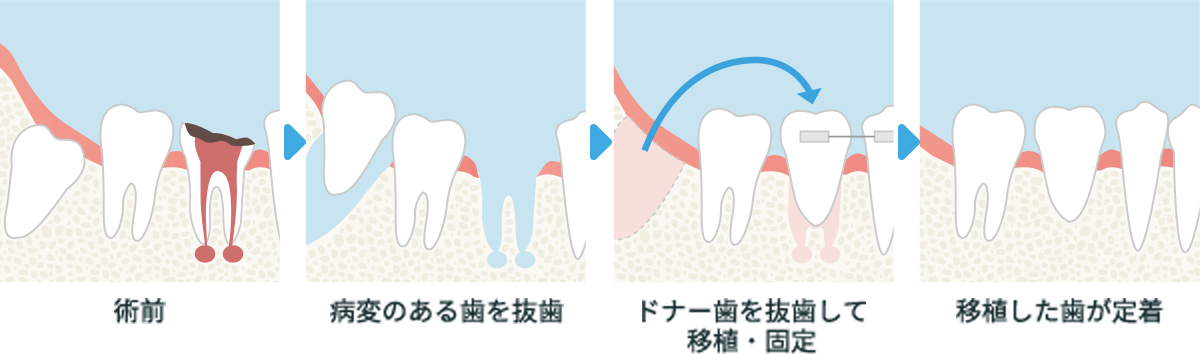

自家歯牙移植(歯の移植)

抜歯を免れないほど、病状が進んでしまった場合、奥歯であれば親知らずを移植する方法を適用することができます。病変がある歯を抜歯して、そこに親知らずを移植し、定着させます。ブリッジやインプラントにせずに済む治療です。

横スクロールで確認いただけます。